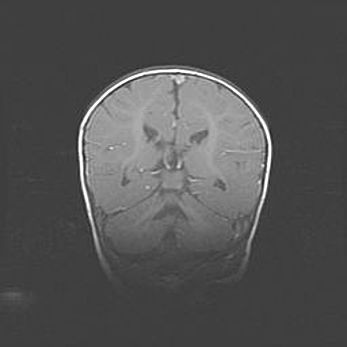

Сообщающаяся гидроцефалия. Кистозная энцефаломаляция головного мозга.

Возраст: 3 месяца 4 дня

Вес: 3100 г

Пол: женский

Окружность головы: 34 см

Срок гестации: 31 неделя

Кистозная энцефаломаляция головного мозга - одна из форм поражения головного мозга в детском возрасте. Характеризуется возникновением множественных и распространённых кист в коре, белом веществе и подкорковых образованиях головного мозга у плодов, новорождённых и детей раннего возраста. Развитие кистозной энцефаломаляции связано с внутриутробной асфиксией и гипотонией, родовой травмой, тромбозом синусов, пороками развития сосудов, инфекциями, сепсисом и другими причинами. Наиболее значимые инфекционные агенты: вирусы простого герпеса, цитомегалии, краснухи, токсоплазмы, энтеробактерии, золотистый стафилококк и другие.